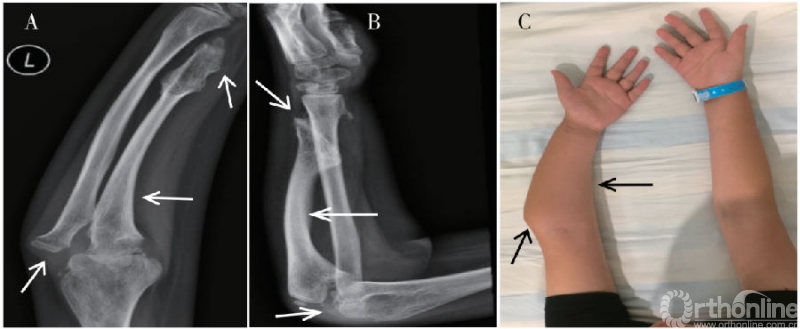

前臂畸形导致外观异常是患儿就诊的主要原因。30%-60%的MHE患者出现不同程度的前臂畸形,出现尺骨生长迟缓、尺桡骨弯曲、下尺桡关节脱位等一系列病理改变,临床表现为尺骨短缩,腕、肘关节畸形和活动障碍(图1)。

图1. 典型多发性遗传骨软骨瘤病患者